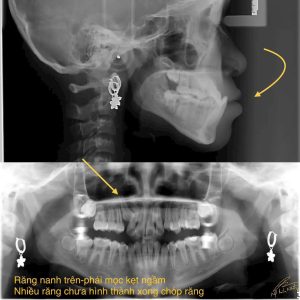

Niềng răng rất phức tạp?

Niềng răng có thể là một quá trình khá phức tạp và đòi hỏi kiên nhẫn. Mức độ khó khăn của việc niềng răng phụ...